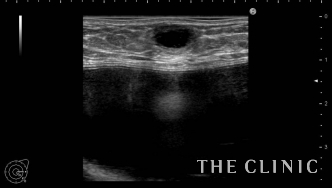

他院にてヒアルロン酸豊胸・バッグ豊胸を受けられ、その直後からしこりが触れはじめたとのこと。豊胸を受けたクリニックでは取り合ってもらえず、更に他院へ相談するがバッグが入っているため処置は難しいと言われ、当院を受診されました。 しこりの大きさは1cmですが、被膜を形成しています。

ヒアルロン酸のしこりのすぐ下にシリコンバッグ がありますのでバッグを損傷しないように注意する必要があります。 エコー下にて確実にヒアルロニダーゼをしこり内に注入し、その後ヒアルロン酸を吸引除去します。